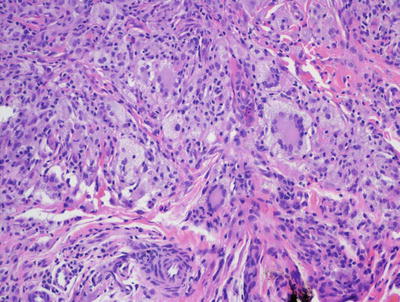

Reticulohistiocytoma demonstrates a nodular proliferation of epithelioid histiocytes within the superficial and mid-dermis [38, 39] (Fig. 22.12). This has given rise to the alternate name of epithelioid histiocytoma. The epidermis is either unremarkable or slightly compressed by the dermal infiltrate. Ulceration is distinctly uncommon. The infiltrate consists predominantly of mononuclear histiocytes with abundant granular and eosinophilic cytoplasm (Fig. 22.13). Other cells may contain varying amounts of cytoplasmic lipid. Multinucleated cells, including Touton giant cells, may be encountered, but they are less abundant than in xanthogranulomas. A smaller population of spindle-shaped histiocytes is often seen within the infiltrate. Mitoses are seen in small numbers, but no atypical forms are expected. Admixed lymphocytes, neutrophils, and scattered eosinophils are present. Older lesions have interspersed fibrosis.

Fig. 22.12

The dermis is filled with an aggregation of large pale-staining histiocytes admixed with inflammatory cells in reticulohistiocytoma

Fig. 22.13

Reticulohistiocytoma is characterized by large mononuclear histiocytes with oncocytic, focally granular cytoplasm and associated inflammatory infiltrate, often with abundant eosinophils. Cytoplasmic lipid is not as prevalent as in xanthogranuloma